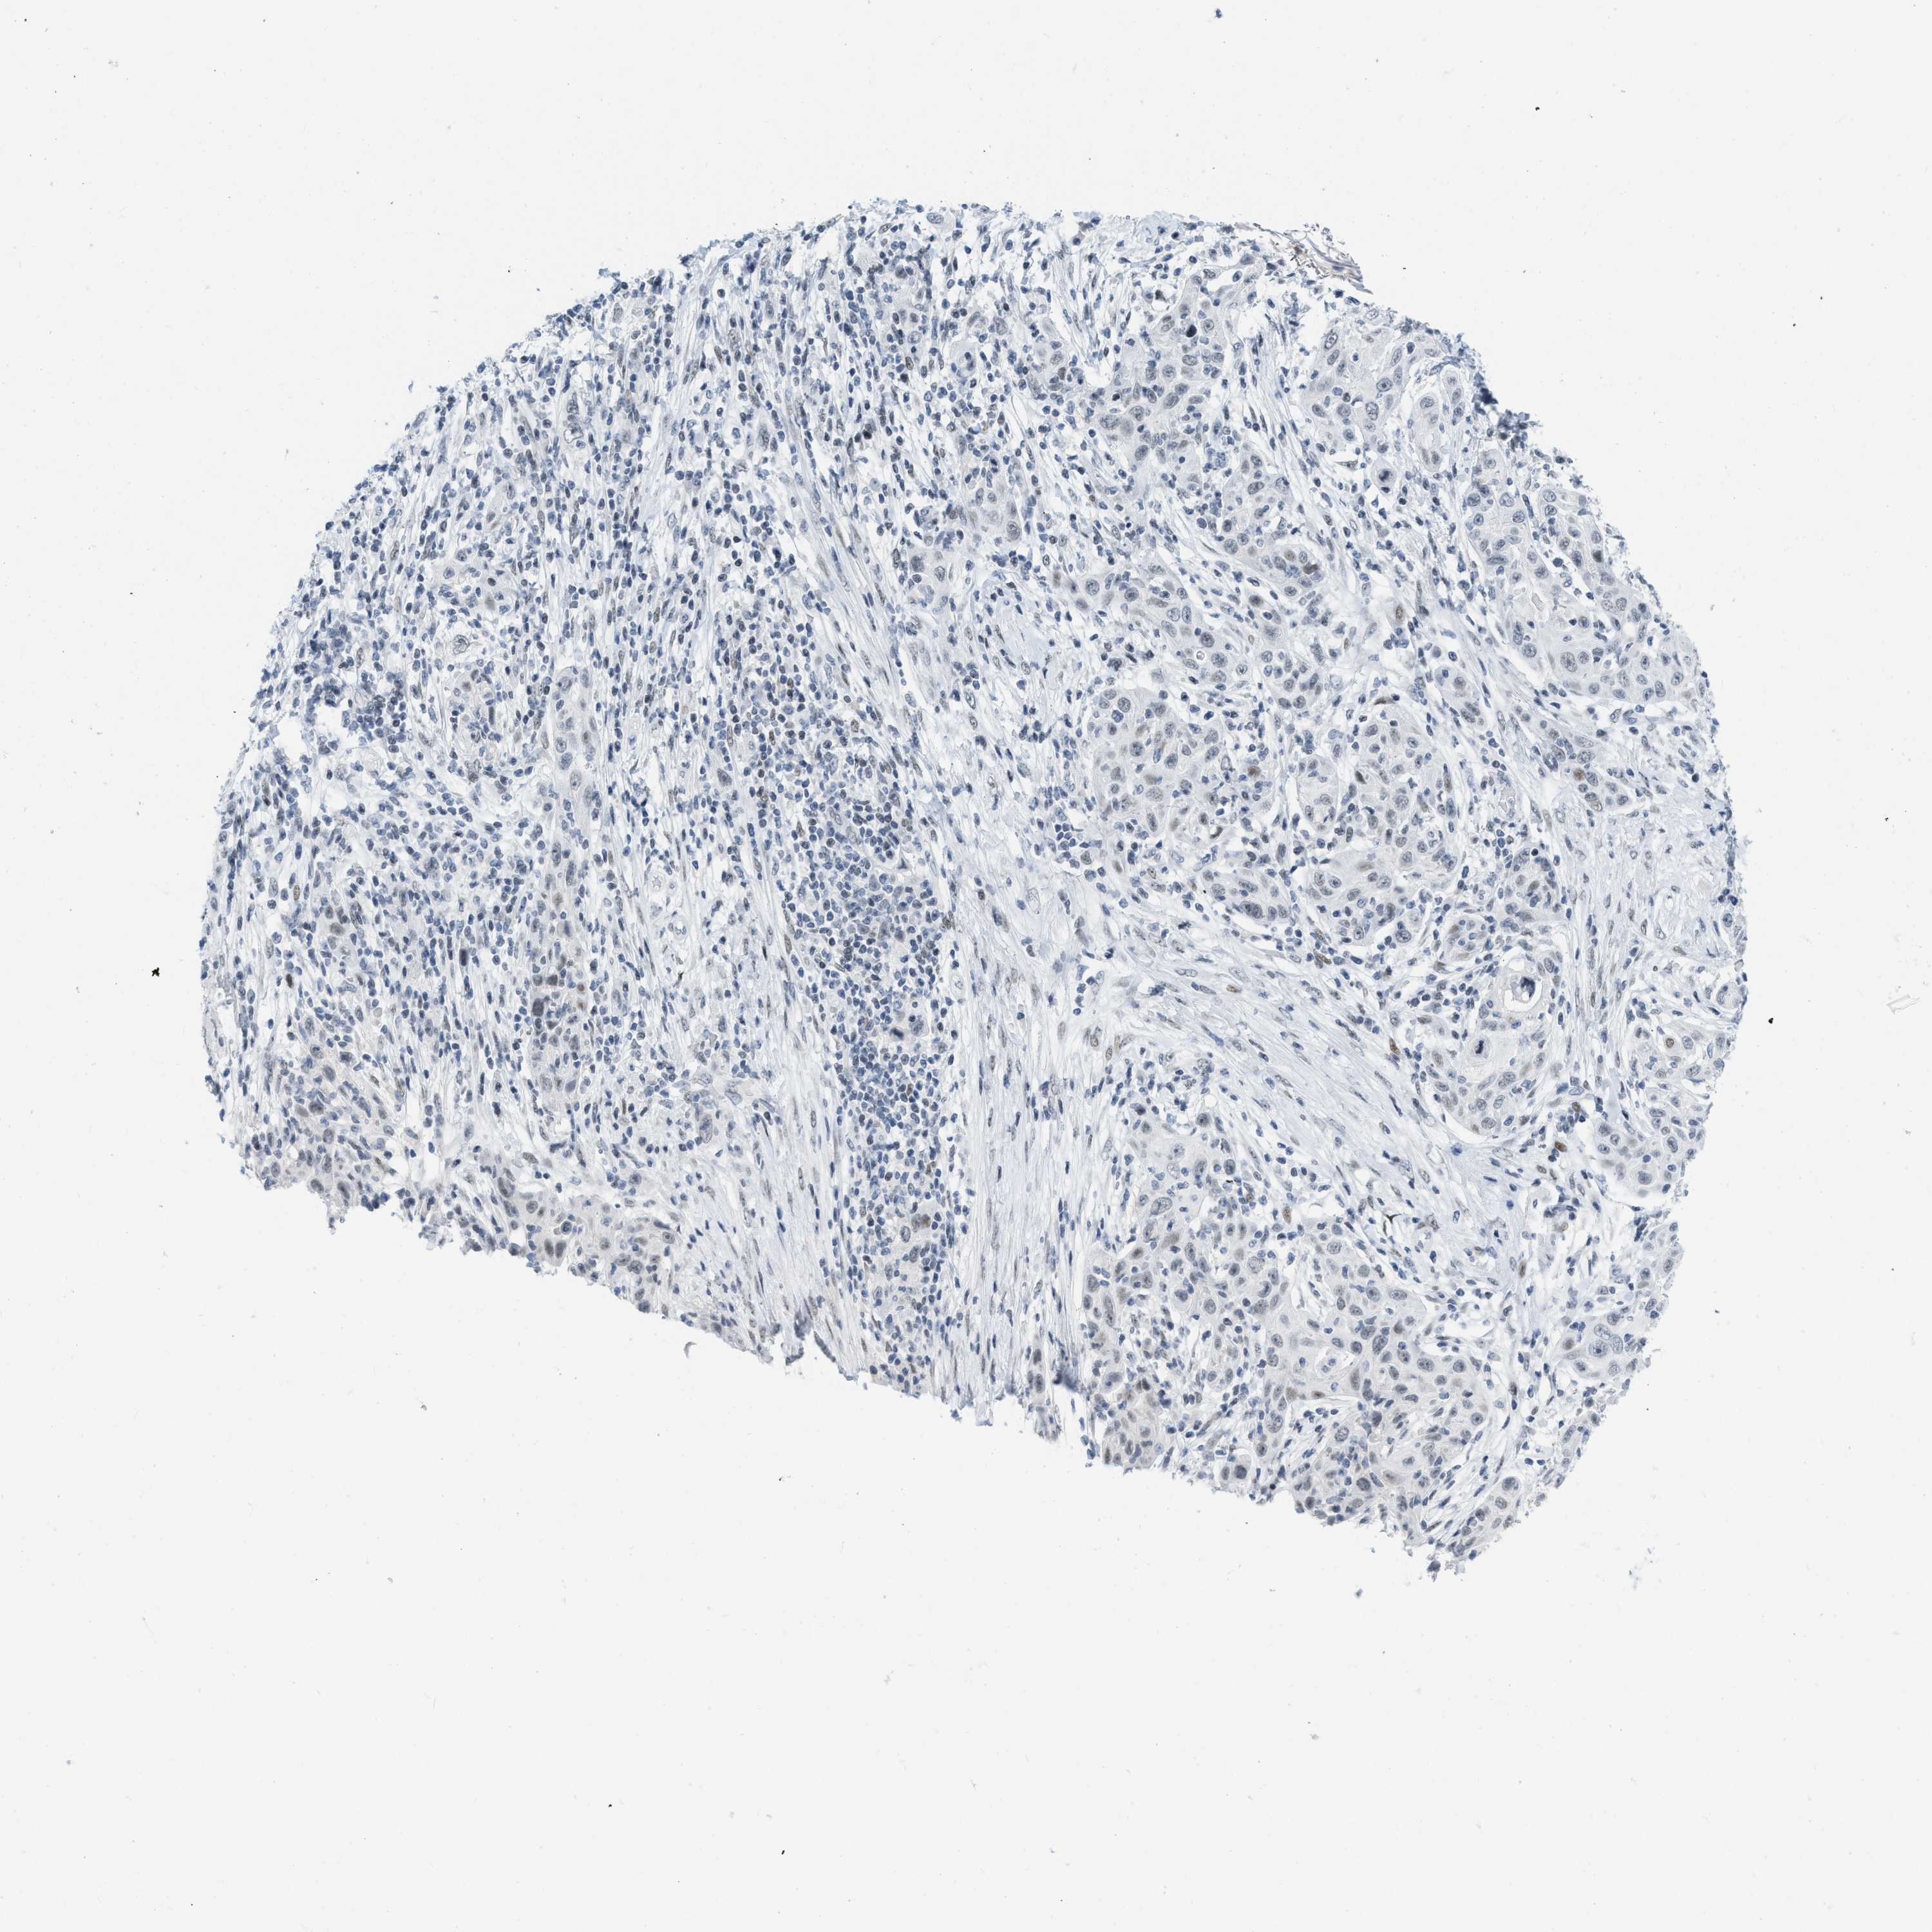

SKIN CANCER - Protein expressioni

A mouse-over function shows sample information and annotation data. Click on an image to view it in a full screen mode. Samples can be filtered based on level of antibody staining by selecting one or several of the following categories: high, medium, low and not detected. The assay and annotation is described here.

Each image is clickable and will lead to virtual microscopy that enables deeper exploration of all samples and also displays staining intensity scores, fraction scores and subcellular localization as well as patient and tissue information for each sample.

Antibody HPA003505

Squamous cell carcinoma, NOS

Basal cell carcinoma

Squamous cell carcinoma in situ, NOS

Squamous cell carcinoma, metastatic, NOS